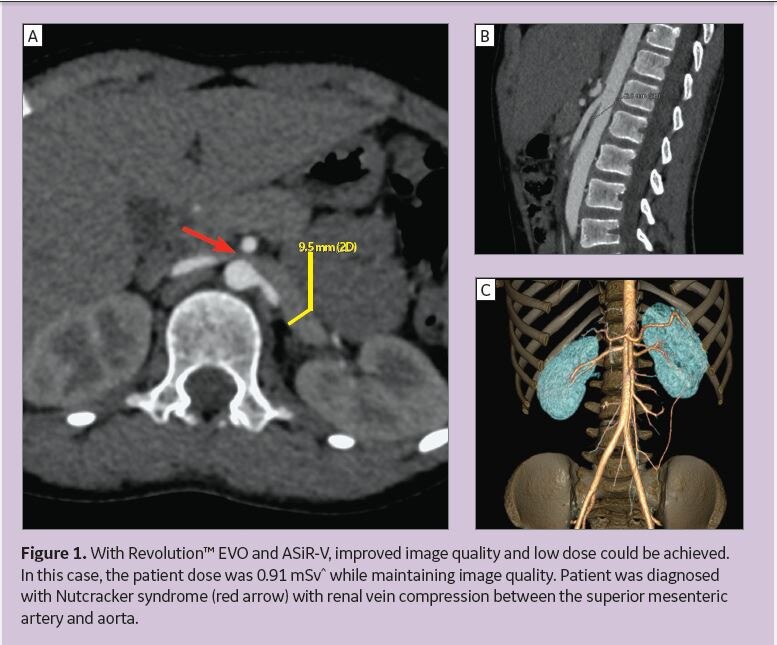

From www.gehealthcare.com

Lowdose Pediatric CT Imaging Helps Detect Nutcracker Syndrome GE Nutcracker Syndrome Icd 9  In this case, the compression of your renal vein causes. Nutcracker syndrome (ncs) describes the symptomatic compression of the left renal vein (lrv) 1 between the aorta and. Nutcracker syndrome refers to the phenomenon when it occurs with symptoms. Specifically, it reviews the latest evidence base for diagnosing nutcracker syndrome using a combination of history and clinical examination, as well. Nutcracker Syndrome Icd 9.